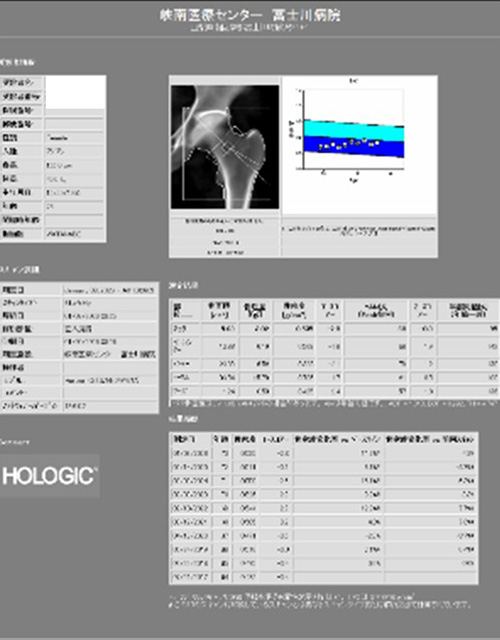

骨密度測定

骨を構成するカルシウムなどのミネラル成分の量をX線を用いて測定する検査です。主に骨粗しょう症の診断や投薬治療による骨量の変化に用います。当院では2つの異なるX線エネルギーを使用する測定法のDEXA法を用いて腰椎、大腿骨の骨密度を測定します。検査時間は10分から15分くらいになります。